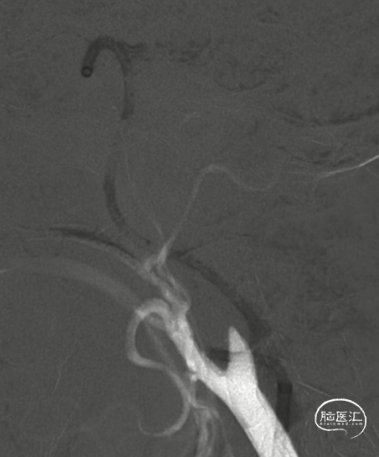

术前造影

右侧颈内动脉闭塞,同时颈外动脉有血栓,闭塞。

右侧颈内动脉起始部呈现“火焰征”,提示假性闭塞,远端眼动脉未见代偿。

前交通开放,左侧A1供应双侧A2。

后交通动脉开放,右侧大脑中动脉可见部分显影。

提示病变为栓塞性串联病变,增加手术难度。这样我们就考虑首先争取单纯抽吸快速开通颈内动脉,然后再SWIM技术取通大脑中动脉。